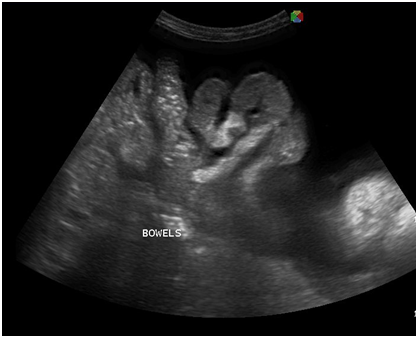

With the four‒month history of rapid abdominal enlargement and significant weight loss, the admitting impression was that of an ovarian new growth probably malignant. However, ultrasound showed only a left adnexal mass described as irregular tubular hyperechoic structure with scattered echogenic stipplings within, densely adherent to the postero‒lateral wall of the uterus, adjacent bowel loops and pelvic sidewalls, while the right ovary appeared grossly normal. Incidentally, there were multiple echogenic foci seen at inferior lobe and parenchyma of the liver, and massive anechoic free fluid was seen in the abdominopelvic cavity. A chest radiograph was also done, which showed pleural effusion on the right; findings suggestive of pulmonary tuberculosis, minimal disease. Work up for tuberculosis was done (Figures 2‒10).

Figure 5 Transabdominal view showing massive anechoic free fluid in the abdominopelvic cavity (ascites) and pallisading bowels.